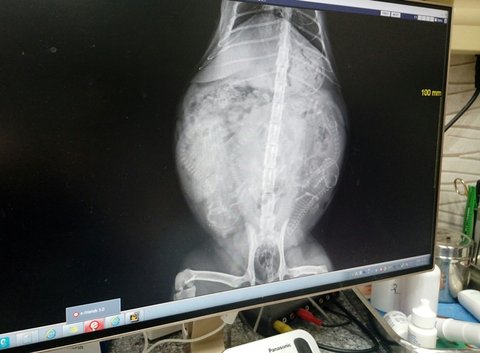

출산준비를 하려면 초음파랑 엑스레이랑 찍어봐야 한다해서 동물병원 가는길

얼추 4마리

혹은 5마리 랍니다.

4마리 같지만 5마리일수도 있다던,,

일단 엑스레이 찍은건 저도 와이프도 생각을 못했습니다ㅠ

처음엔 초음파만 찍으면 될줄알았는데

병원에 물어보니 엑스레이를 찍어야 몇마리인지 알수있다 하더라구요